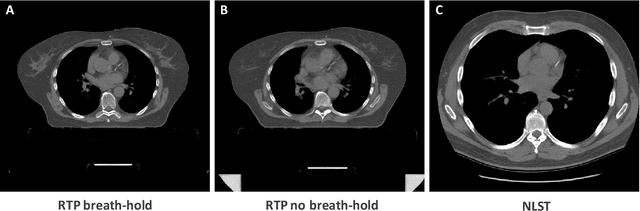

Abstract:Purpose: Coronary artery calcium (CAC) score, i.e. the amount of CAC quantified in CT, is a strong and independent predictor of coronary heart disease (CHD) events. However, CAC scoring suffers from limited interscan reproducibility, which is mainly due to the clinical definition requiring application of a fixed intensity level threshold for segmentation of calcifications. This limitation is especially pronounced in non-ECG-synchronized CT where lesions are more impacted by cardiac motion and partial volume effects. Therefore, we propose a CAC quantification method that does not require a threshold for segmentation of CAC. Approach: Our method utilizes a generative adversarial network where a CT with CAC is decomposed into an image without CAC and an image showing only CAC. The method, using a CycleGAN, was trained using 626 low-dose chest CTs and 514 radiotherapy treatment planning CTs. Interscan reproducibility was compared to clinical calcium scoring in radiotherapy treatment planning CTs of 1,662 patients, each having two scans. Results: A lower relative interscan difference in CAC mass was achieved by the proposed method: 47% compared to 89% manual clinical calcium scoring. The intraclass correlation coefficient of Agatston scores was 0.96 for the proposed method compared to 0.91 for automatic clinical calcium scoring. Conclusions: The increased interscan reproducibility achieved by our method may lead to increased reliability of CHD risk categorization and improved accuracy of CHD event prediction.